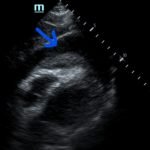

Focused assessment with sonography in trauma (FAST) scan was positive for a clinically significant pericardial effusion as evidenced by the hypoechoic fluid around the myocardium, indicated by the blue arrow in image 2. Findings are also consistent with tamponade process as evidenced by restricted expansion and collapse of the right ventricle during diastole. The hyperechoic floating structure between the pericardium and myocardium, adjacent to the right ventricle, represents a pericardial clot, indicated by the white arrow.The density of the pericardial clot differs from that of the myocardium, thus serving as an additional variable to avoid confusing this as part of the myocardial structure.